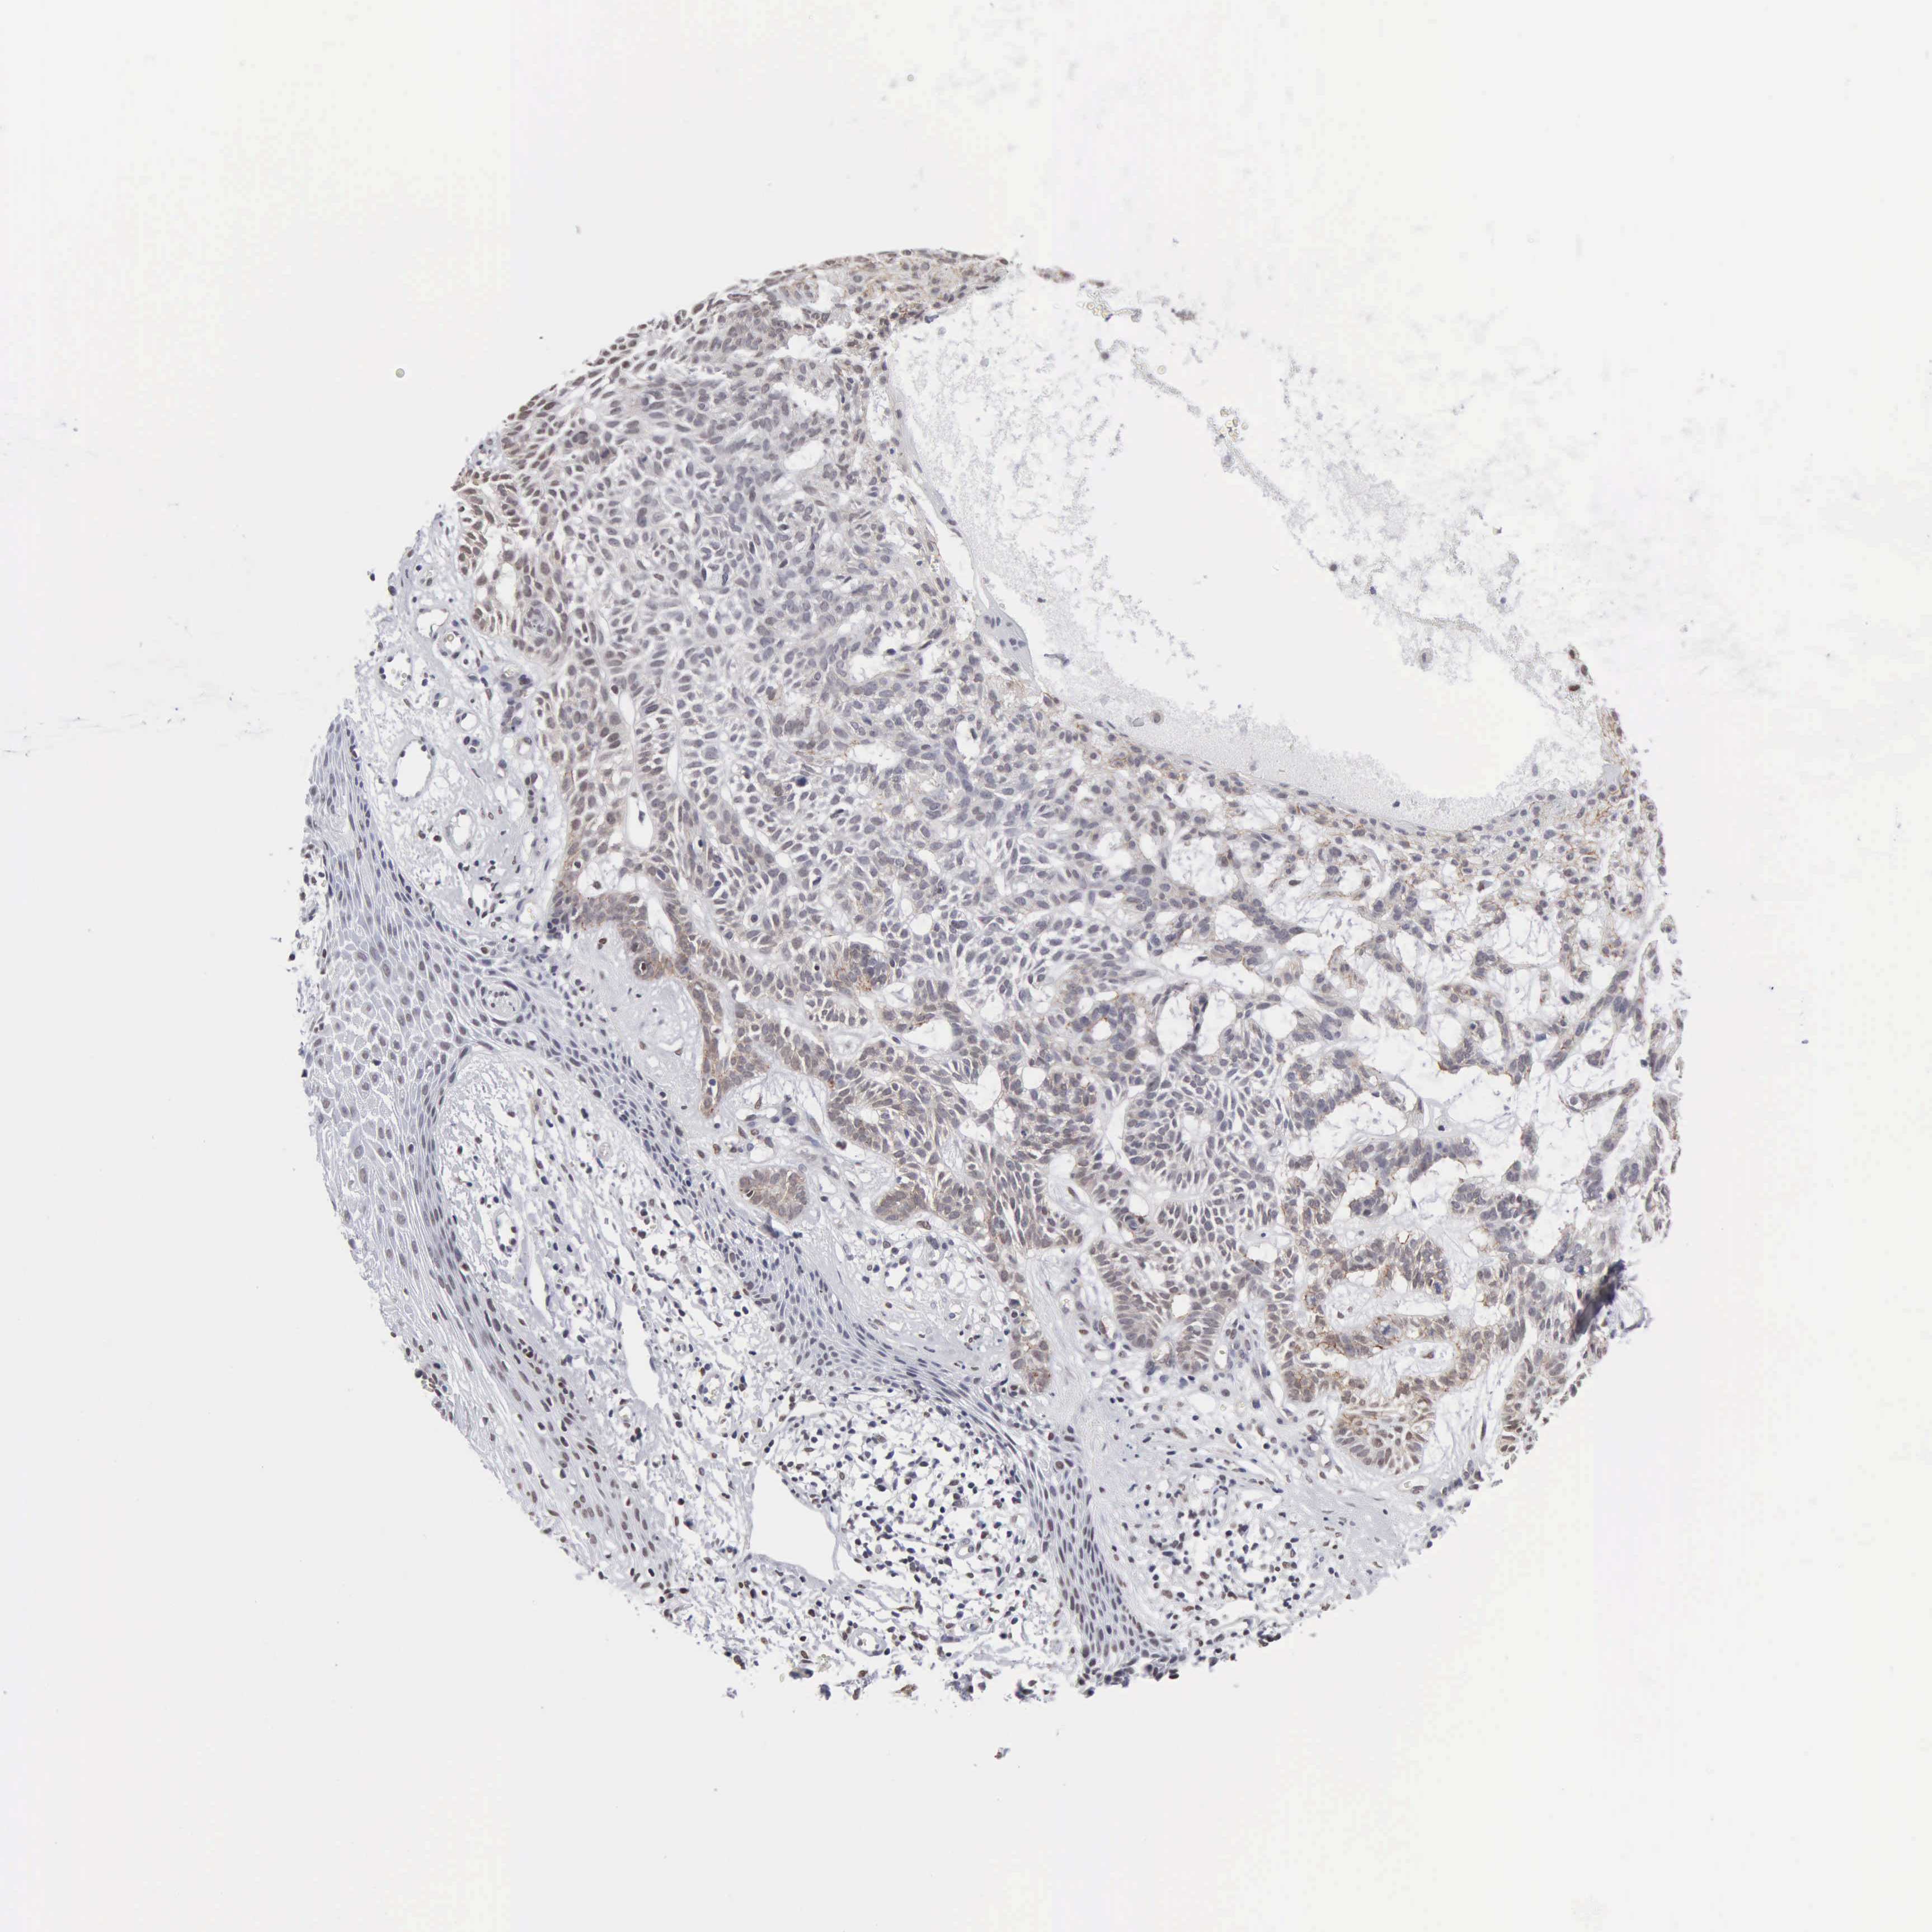

SKIN CANCER - Protein expressioni

A mouse-over function shows sample information and annotation data. Click on an image to view it in a full screen mode. Samples can be filtered based on level of antibody staining by selecting one or several of the following categories: high, medium, low and not detected. The assay and annotation is described here.

Antibody staining in the annotated cell types in the current human tissue is reported as not detected, low, medium, or high, based on conventional immunohistochemistry profiling in selected tissues. This score is based on the combination of the staining intensity and fraction of stained cells.

Each image is clickable and will lead to virtual microscopy that enables deeper exploration of all samples and also displays staining intensity scores, fraction scores and subcellular localization as well as patient and tissue information for each sample.

Antibody CAB000350

Staining

High

Medium

Low

Not detected

Intensity

Strong

Moderate

Weak

Negative

Quantity

>75%

75%-25%

<25%

None

Location

Nuclear

Cytoplasmic/membranous

Cytoplasmic/membranous,nuclear

Squamous cell carcinoma, NOS

Basal cell carcinoma